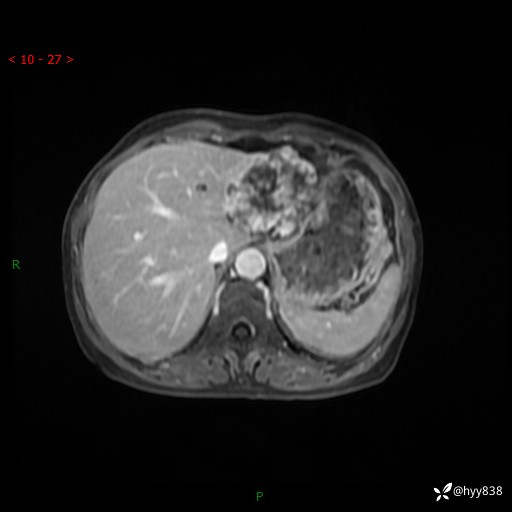

老年女性,偶然发现肝脏占位,综合各个序列,你考虑什么---结果公布

主诉:发现肝脏占位性病变2天

简要病史:患者2天前因“腰疼”至当地医院就诊时发现肝脏左叶占位性病变,无发热、畏寒,无皮肤黄染,无腹痛、腹泻,无恶心、呕吐、厌油等不适,今进一步诊治遂来我院就诊,门诊以“肝脏占位性病变性质待查”收入我科。 起病以来,患者精神、睡眠一般,饮食欠佳,二便正常,体力、体重无明显减轻,

辅助检查:MRI

临床诊断:肝占位

肝脏MRI平扫(同反相位)

T2WIfs+DWI

增强(动脉期+静脉期+延迟期)